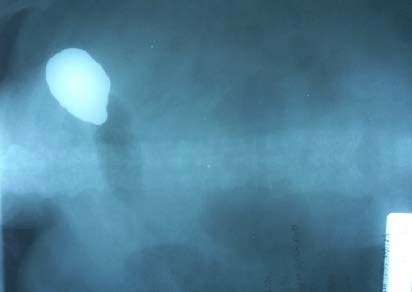

Пациентка В., 58 лет, поступила в хирургическое отделение БУЗ УР «Первая республиканская клиническая больница Министерства здравоохранения Удмуртской Республики», г. Ижевск, 11.03.2024 с диагнозом «острый билиарно-алкогольный панкреатит». При поступлении предъявляла жалобы на умеренные боли в правом подреберье, эпигастральной и пупочной областях, тошноту, периодическую рвоту желудочным содержимым. Заболела остро 02.02.2024, появились интенсивные ноющие боли в правом подреберье, затем по всему животу. До этого злоупотребляла алкоголем, отмечалась желтуха, ахолия кала, повышение температуры тела до 380С. Находилась на лечении в хирургическом отделении Центральной районной больницы до 09.02.2024, где при УЗИ были обнаружены камни в желчном пузыре. Для дальнейшего лечения была переведена в межрайонную больницу, где находилась на лечении до 11.03.2024 с диагнозом «субтотальный асептический панкреонекроз. Парапанкреатический инфильтрат. Механическая желтуха. Формирование кисты поджелудочной железы. Желчнокаменная болезнь, хронический калькулезный холецистит». На фоне лечения желтуха разрешилась, самочувствие улучшилось, температура тела нормализовалась. По данным УЗИ, СКТ в области головки поджелудочной железы сформировалось жидкостное образование. При пальпации в эпигастральной области определялся инфильтрат 8,0´15,0 см, болезненный, неподвижный, с сомнительной флюктуацией. Пациентке предложено оперативное лечение. Выполнена (13.03.2024) лапароскопическая санация и дренирование сальниковой сумки, частичная некрсеквестрэктомия. С 15.03.2024 больная стала отмечать усиление жалоб на тошноту и рвоту выпитой жидкостью и желудочным содержимым с примесью желчи. С 17.03.2024 рвота стала многократной. Учитывая частую рвоту с целью исследования транзита назначена и проведена проба Шварца с сульфатом бария. На 19.03.2024 контраст сохраняется в желудке в течение суток (рис. 1).

Рис. 1. Проба Шварца